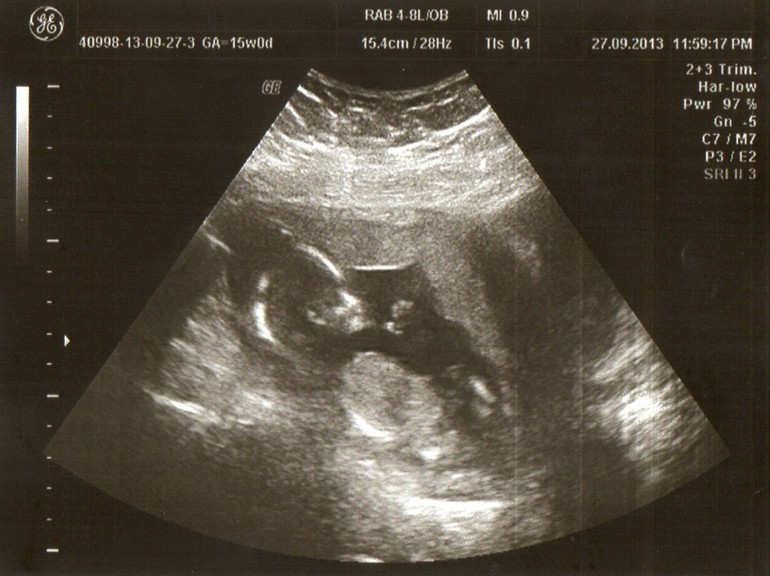

2 недели назад ....мое УЗИ!!!!!

УЗИ, КТГ, доплерДелала в 15 недель УЗИ платно,т.к. совсем не понравилось как сделали 1 скрининг в ЖК,мне уделили ровно 3мин,и за это время сказали что все ок,а какие размеры,параметры и тд самое важное не сказали... Плюнула я на все это дело и пошла сделала нормальный скрининг в платную клинику.Осталась довольна как слон!!!Мало того что облизали с ног до головы,уделили время мне,поговорили о самочувствиии что принимаю и тд,при этом повторюсь пришла не на консультацию а на УЗИ а получила 2 в 1.По показателям все в норме на тот момент соответствовало все 15 неделям,где-то даже немного опережал мой деть....пол ребенка под вопросом в один момент пуповина между ножек лежала,в другой момент сказали вроде девочка,но гарантии нет ...Поэтому Ждемс!!!Ну и мой ребятенок в 15 неделек!!!!!